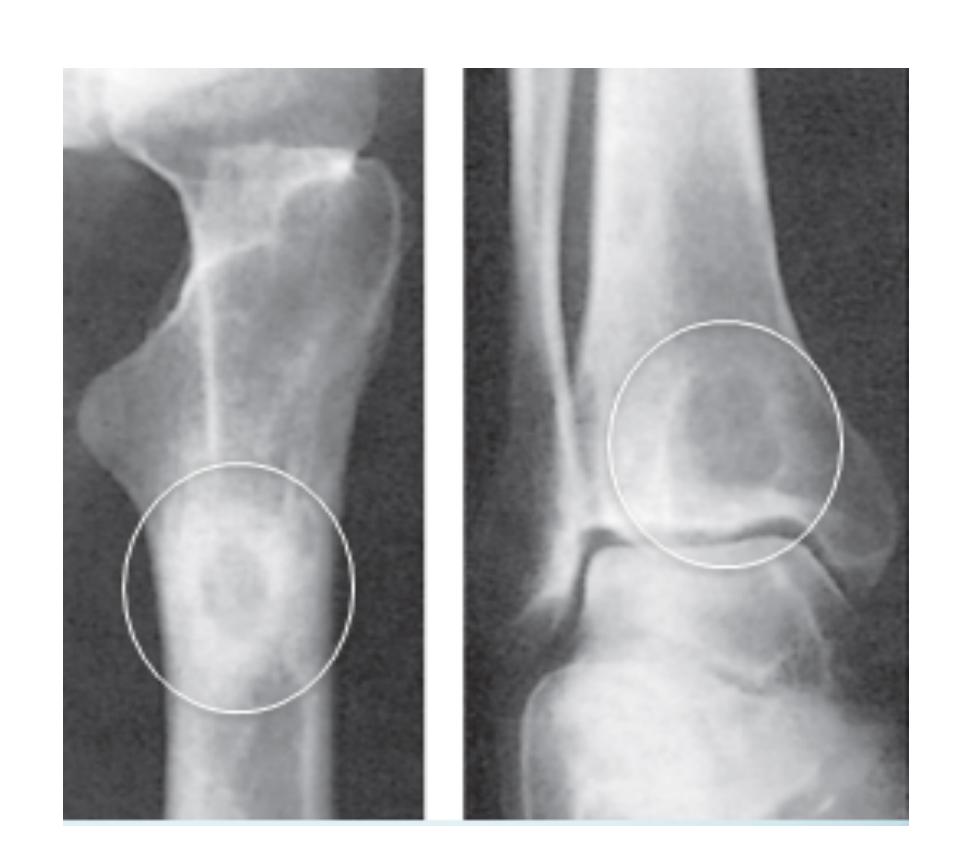

Examination of HIP

| Item | Procedure | Additional Information … | Attachments |

| Special tests | - Thomas test | Purpose: Detect fixed flexion deformity of the hip. Positive Thomas test in neonates and young children is normal. Procedure: Assess lumbar lordosis before testing. Precaution: When knee has fixed flexion deformity, keep knee outside edge of couch. | Thomas Test (Precaution)![]() Thomas Test (Solution) ![]() |

| - Trendelenburg test | Purpose: Assess hip abductor strength and stability. Principle: Testing the hip the patient is standing on. Normal: Pelvis tilts down on weight-bearing hip (performed by hip abductors). Positive: Pelvis on non-weight-bearing hip tilts down AND trunk tilts to weight-bearing side. Causes of Positive Trendelenburg: Weak hip abductors, mechanically inefficient hip abductors, unstable pivot of motion, inhibited hip abductors (painful), reduced range of motion. Note: Almost any hip disease can cause a positive Trendelenburg test. | Trendelenburg Test setup![]() Trendelenburg Test execution ![]() Normal vs Positive comparison ![]() Trendelenburg Test detailed ![]() Trendelenburg results ![]() | |

| - Leg length: True / Apparent | Galleazzi Test Purpose: Detect leg length discrepancy. Technique: Both heels must be at the same level. Apparent Length: Measurement: Midpoint to medial malleolus. Affected by: Pelvic tilt. Both lower limbs - Should be Parallel. True Length: Measurement: ASIS to medial malleolus. Not affected by Pelvic tilt. Position of both lower limbs - Should be identical. | Galleazzi ![]() Galleazzi ![]() Purpose: Detect leg length discrepancy Technique: Both heels must be at the same level ---- ![]() Apparent length measurement - Measurement: Midpoint to medial malleolus - Affected by: Pelvic tilt ![]() True length measurement - Measurement: ASIS to medial malleolus - Not affected by Pelvic tilt ![]() ![]() | |